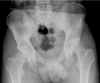

Background: Acetabular fractures still are among the most challenging fractures to treat because of complex anatomy, involved surgical access to fracture sites and the relatively low incidence of these lesions. Proper evaluation and surgical planning is necessary to achieve anatomic reduction of the articular surface and stable fixation of the pelvic ring. The goal of this study was to test the feasibility of preoperative surgical planning in acetabular fractures using a new prototype planning tool based on an interactive virtual reality-style environment.

Methods: 7 patients (5 male and 2 female; median age 53 y (25 to 92 y)) with an acetabular fracture were prospectively included. Exclusion criterions were simple wall fractures, cases with anticipated surgical dislocation of the femoral head for joint debridement and accurate fracture reduction. According to the Letournel classification 4 cases had two column fractures, 2 cases had anterior column fractures and 1 case had a T-shaped fracture including a posterior wall fracture.The workflow included following steps: (1) Formation of a patient-specific bone model from preoperative computed tomography scans, (2) interactive virtual fracture reduction with visuo-haptic feedback, (3) virtual fracture fixation using common osteosynthesis implants and (4) measurement of implant position relative to landmarks. The surgeon manually contoured osteosynthesis plates preoperatively according to the virtually defined deformation. Screenshots including all measurements for the OR were available.The tool was validated comparing the preoperative planning and postoperative results by 3D-superimposition.

Results: Preoperative planning was feasible in all cases. In 6 of 7 cases superimposition of preoperative planning and postoperative follow-up CT showed a good to excellent correlation. In one case part of the procedure had to be changed due to impossibility of fracture reduction from an ilioinguinal approach. In 3 cases with osteopenic bone patient-specific prebent fixation plates were helpful in guiding fracture reduction. Additionally, anatomical landmark based measurements were helpful for intraoperative navigation.